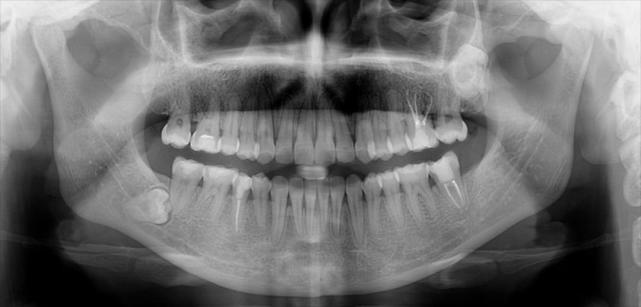

曲面体层片正常结构

曲面体层片正常结构,人体结构

曲面体层及cbct显示小王口腔右侧下颌有一个阻生智齿,需要尽快拔除!

牙体硬组织疾病牙片:全口牙为曲面体层片:下颌可见解剖结构:上颌可见

22,23,35,45,31,41先天缺失(cbct图;a~d为矢状位;e为重建曲面体层片